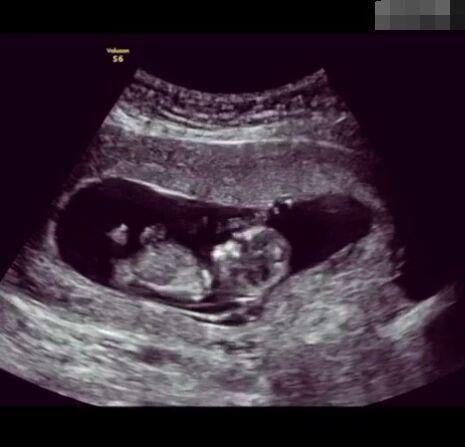

孕育生命是一件無比非凡的事!想像一下,我們都是從一個肉眼難見的小小受精卵發(fā)育而來,而這只需要一顆卵子與一顆精子的結合,就能實現(xiàn)一個生命的從無到有的過程,這是多么神奇的一件事情!

圖片2.png